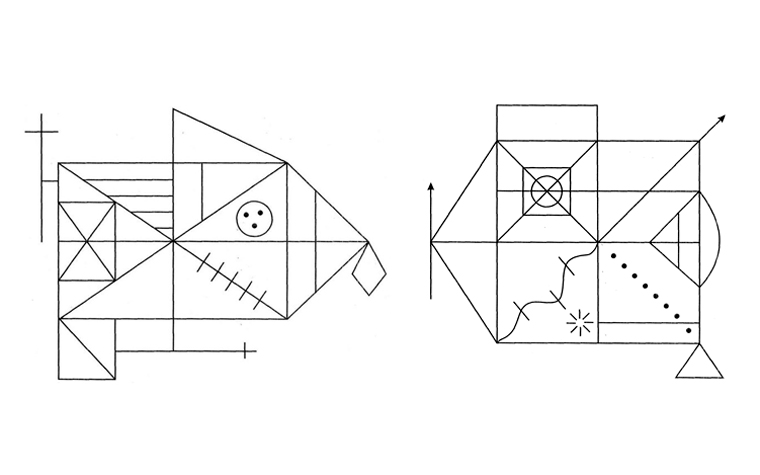

Общепсихологический анализ молитвы в работах Ф.Е. Василюка26.08.2021В области психологии духовность приобретает прагматический смысл и подчас превращается в своеобразные вариации психотехник по решению личностных проблем и улучшению качества жизни. Такая колонизация религиозного характерна и для обыденного сознания… Методика «Комплексная фигура»: диагностика нейрокогнитивного дефицита25.08.2021Методика «Комплексная фигура» Рея — Остерриета используется для диагностики нейрокогнитивного дефицита в целях дифференциального диагноза, функционального прогноза и мониторинга динамики и коррекции когнитивных дисфункций у детей и взрослых...

Методика «Комплексная фигура»: диагностика нейрокогнитивного дефицита25.08.2021Методика «Комплексная фигура» Рея — Остерриета используется для диагностики нейрокогнитивного дефицита в целях дифференциального диагноза, функционального прогноза и мониторинга динамики и коррекции когнитивных дисфункций у детей и взрослых... О лаборатории «Восприятие» и прогнозах развития VR-технологий24.08.2021Беседа с Елизаветой Геннадьевной Луняковой, старшим научным сотрудником лаборатории «Восприятие» факультета психологии МГУ им. М.В.Ломоносова о прошлом, настоящем и будущем VR-технологий.